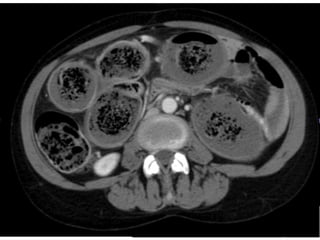

Colonic scleroderma

Motility:

Reduced colonic transit time.

Radiology:

Colonic dilatation.

Loss of haustration.

Pseudo-sacculation.